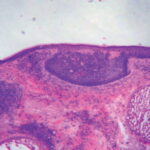

Superficial Basal Cell Carcinoma

Superficial BCC is characterized microscopically by buds of malignant cells extending into the dermis from the basal layer of the epidermis. The peripheral cell layer shows palisading. There may be epidermal atrophy, and dermal invasion is usually minimal. This histologic sub-type is encountered most often on the trunk and extremities but may also appear on the head and neck. There may be a chronic inflammatory infiltrate in the upper dermis.